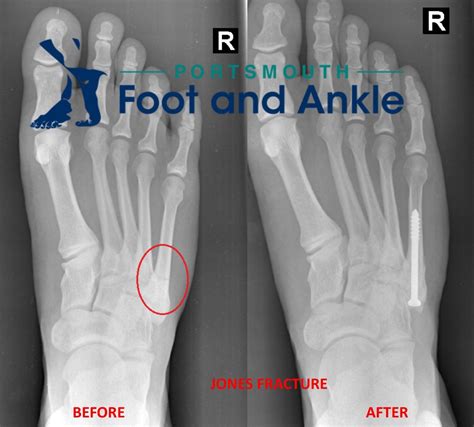

• Imaging Tests: X-rays are the most common imaging test used to diagnose fractures. However, hairline fractures may not always be visible on initial X-rays. In such cases, additional imaging tests such as MRI or CT scans may be required.

Surgical intervention is typically reserved for severe cases where the fracture is unstable or does not heal properly with non-surgical treatment. Surgery may involve:

• Open Reduction and Internal Fixation (ORIF): This procedure involves realigning the bone fragments and securing them with screws, plates, or rods.